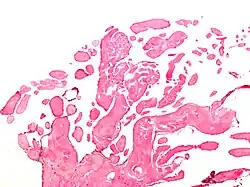

| Micrograph of a papillary fibroelastoma, a benign tumor of heart valves. H&E stain. | |

- Papillary fibroelastoma

A subset of the primary tumors of the heart are tumors that are found on the valves of the heart. Tumors that affect the valves of the heart are found in an equal distribution among the four heart valves.[2] The vast majority of these are papillary fibroelastomas. Primary tumors of the valves of the heart are more likely to occur in males. While most primary tumors of the valves of the heart are not malignant, they are more likely to have symptoms related to the valve, including neurologic symptoms and (in a few cases) sudden cardiac death.